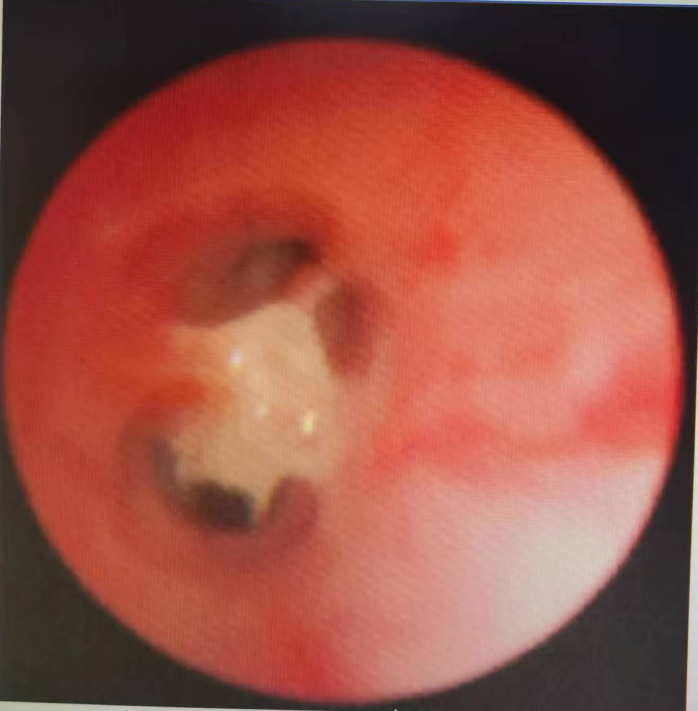

(气管镜下取出龋齿)

小炫,男,11岁9月,因反复咳嗽5年入院,完善胸部CT检查,影像学诊断右主支气管近段管腔内金属影,遂入院行“支气管镜气管异物取出术+肺泡灌洗术”,术中取出一枚锈迹斑斑的图钉,术后咳嗽症状消失。

(绿色箭头为异物)

(气管镜下取出图钉)